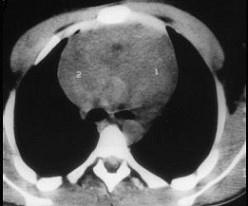

问题 血友病患者突发胸闷,气急,体查见颈静脉显露,嘴唇发干,影像学检查如图,最可能的诊断为 ( )

选项 A、纵隔积液 B、胸腺瘤 C、淋巴瘤 D、结节病 E、纵隔自发性出血

答案 E